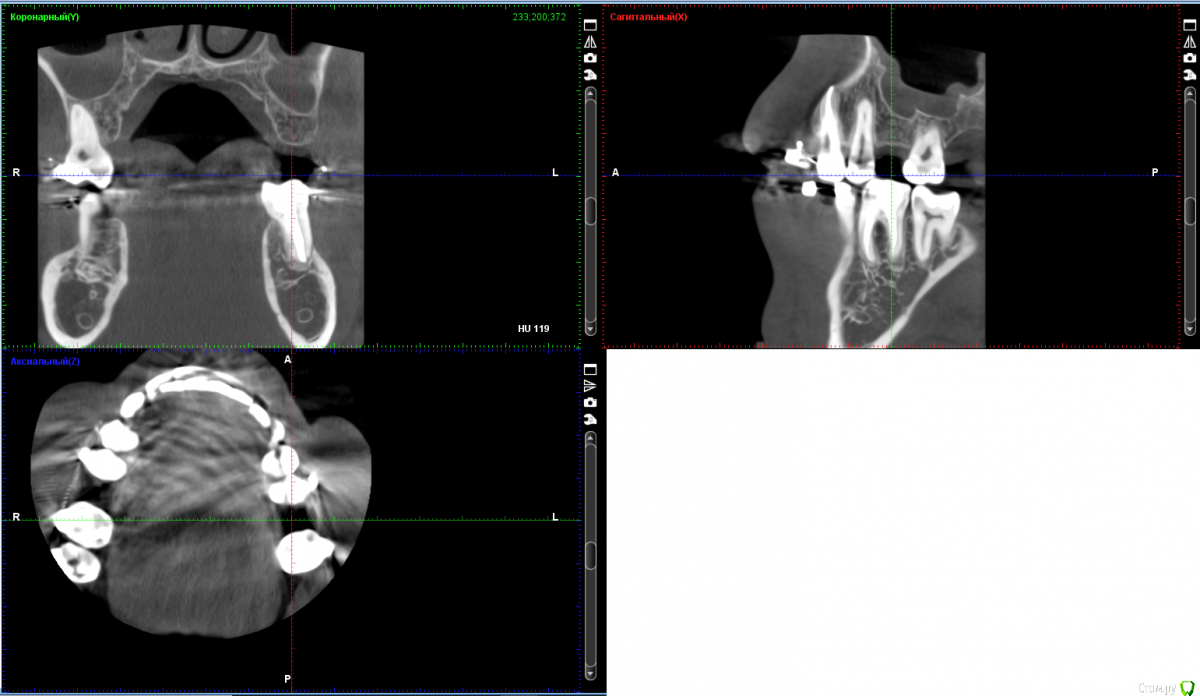

Bors Опубликовано 1 декабря, 2019 Автор Поделиться Опубликовано 1 декабря, 2019 по высоте хватает, ширину нужно смотреть на Кт (качать весь архив не буду) покажите срезы областей интересаСрезы сам не делал, так как не знаю насколько правильными они будут. Прикрепляю то, что получилось. как правило не влияетЯсно. Просто частенько проскакивает в описаниях тех или иных моделей информация о том, что это идеальный вариант при недостатке костной ткани и т.п. Не совсем понятно стоит ли переплачивать за тот же Nobel или выбрать что-то дешевле. Хочется поставить и забыть на всю жизнь про этот зуб. Ссылка на комментарий

red_butler Опубликовано 1 декабря, 2019 Поделиться Опубликовано 1 декабря, 2019 костная пластика не нужна, разве что небольшой закрытый синуслифтинг слева Ссылка на комментарий

Bors Опубликовано 2 декабря, 2019 Автор Поделиться Опубликовано 2 декабря, 2019 Был сегодня на консультации у имплантолога.Работают с двумя системами - MIS и Astra Tech. Остановился я на последней, послушав врача и почитав отзывы. Что касается синус-лифтинга, то по 26-му зубу мне сообщили, что он действительно не нужен, а вот по 16-му что-то вроде пограничного положения. Пока в плане лечения открытый синус-лифтинг предварительно (врач объясняет перестраховкой), но будет известно точно после обсуждения с ортопедом при разработке хирургического шаблона. Возможно будет и закрытый. Ссылка на комментарий

Irouil Опубликовано 3 декабря, 2019 Поделиться Опубликовано 3 декабря, 2019 Что касается синус-лифтинга, то по 26-му зубу мне сообщили, что он действительно не нужен, а вот по 16-му что-то вроде пограничного положения. Все наоборот. Но синус лифт там требуется минимальный. Астра тёк прекрасные имплантаты Ссылка на комментарий